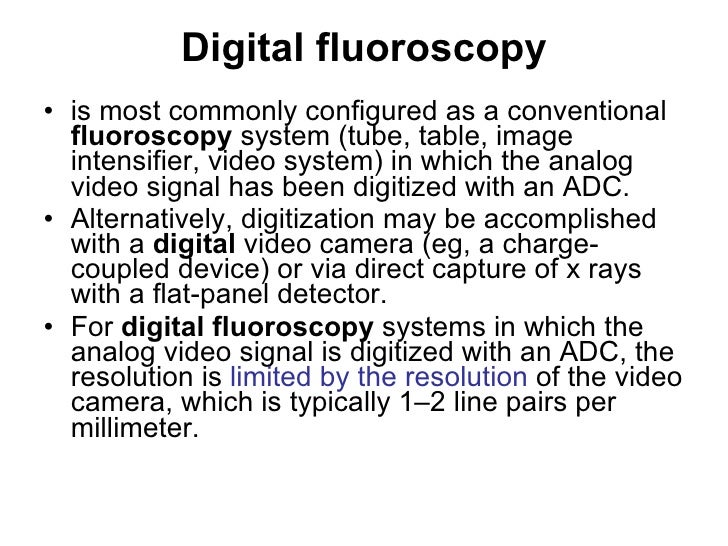

images of the matrix smallest which has size pixels Digital fluoro high quality jpeg wallpaper download

images of has matrix which the size smallest pixels fluoro Digital high quality jpeg wallpaper download

images of the matrix smallest which has size pixels Digital fluoro high quality jpeg wallpaper download

images of has matrix which the size smallest pixels fluoro Digital high quality jpeg wallpaper download